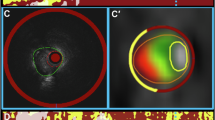

Evaluation of plaque was performed according to the following multi-step protocol, illustrated in Fig. 1. In a first step, five plaques in five consecutive patients were studied to calibrate the HU thresholds of the Plaque Map software to IVUS or IVUS-VH (Fig. 2). Thereby, selection of target lesions in DSCT was interactively performed by reader 1 and 2 who were both de-blinded to the IVUS results of the specific patients. The subsequent adjustment of vessel or plaque volumes with calibration of HU thresholds was done by a de-blinded single reader 1. On CT CPRs, accurate matching of lesions to IVUS was ensured by referring to lesion length and fiduciary markers (stents, side branches or characteristic calcifications) as defined in longitudinally reconstructed IVUS data. A maximal measurement-discrepancy of 5% was accepted with regard to length of segment. The semi-automatic vessel edge definition of the analysis software was employed and, whenever necessary, the vessel boundaries adapted to achieve a close match (±5%) to the vessel volumes in IVUS. Subsequently, the threshold for the calcified plaque component was modified so that its volume equaled the results of IVUS-VH. The lower threshold for the fatty plaque component was always fixed to −10 HU, and the cut-off for the vessel lumen was individually adjusted until the entire plaque burden matched to its volume in IVUS. For the individual adjustment of the cut-off between fatty and fibrous plaque, the relative proportion between the lipid and fibrous component was calculated in IVUS-VH and applied to DSCT through modification of the distinct HU threshold (Fig. 2). HU values for all thresholds were recorded, and the means of these values were used for further analysis of the verification group.

In step 2, analysis of another 15 plaque-containing segments (distributed in 8 patients) was performed by reader 1, who was blinded to the corresponding results in IVUS. As described above, matching of corresponding lesions was ensured by referring to lesion length and fiduciary markers. Again, a maximal measurement discrepancy of 5% was accepted with regard to length of the target lesion. Semi-automatic segmentation of vessel edge was applied and manually adjusted in case of obvious divergence from the outer vessel wall. Using the calibrated HU thresholds, volumes of vessel, lumen as well as low, medium and high density plaque components were automatically displayed by the Plaque Map software. Corresponding colors in the color-coding overlay were dark green for fatty plaque, light green for fibrous plaque and purple for calcified plaque. Yellow was used for vessel lumen.

Virtual plaque histology in DSCT and IVUS. In an axial MIP, the arrow indicates a non-calcified plaque in segment 6 of the LAD (a). Cross-sectional images of the vessel with color coding are presented for visual adjustment of the maps (b) or HU-based segmentation (c) as well as for grey-scale IVUS (d) and IVUS-VH (e). For IVUS-VH, red indicates necrotic core, light green the fatty-fibrous, dark green the fibrous and white the calcified plaque. In this lesion, total plaque volumes with visual CT evaluation, HU-based analysis or IVUS were 66.6 mm3, 55.8 mm3 or 53.1 mm3 respectively